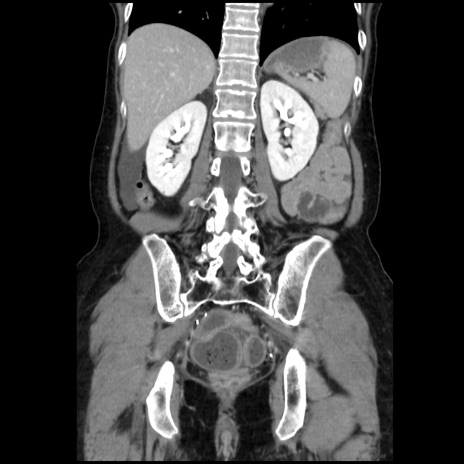

症例32(冠状断像)

【症例】40歳代 女性

【主訴】上腹部痛、嘔気・嘔吐

【現病歴】約9時間前頃から急に上腹部痛、嘔気、嘔吐が出現。改善しないため救急要請。

【既往歴】子宮頚癌(広汎子宮全摘術、放射線療法)、腸閉塞

【身体所見】腹部:平坦、軟、腸雑音亢進、上腹部を中心に腹部全体に圧痛あり。

【データ】WBC 8400、CRP 0.03